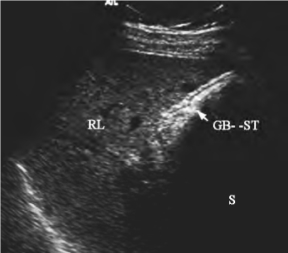

1.29第25章 胆管系统

1.29.1一、胆管系统的解剖

1.29.2二、检查方法

1.29.3三、正常超声表现